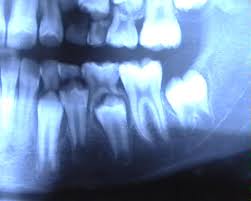

Les premières dents tombent dans un ordre bien précis. Les dents de lait commencent à tomber au bout du quatrième mois, cependant la durée de pousse et la perte de dents de lait varie selon les races progressivement, les dents de lait seront remplacées par les dents d'adulte jusqu'à l'âge de sept mois. On parle plus scientifiquement de dents provisoires.

Les premières dents apparaissent vers l'âge de 6 mois chez le bébé, et c'est ensuite vers les 6 ans de l'enfant que la perte des dents de lait débute. Les dents de lait se font déloger par les dents définitives vers les six ans de l'enfant, parfois cinq ans. Perte / vol de carte vitale.

Le parodonte représente l'ensemble des tissus de soutien des dents : La première dent de devant mignonne que votre bébé a reçue en bref, il est sage pour les parents de surveiller la perte des dents de lait et de noter l'horaire des chutes. Chez l'homme ces dents sont nommées dent déciduale, dent de lait ou dent lactéale.